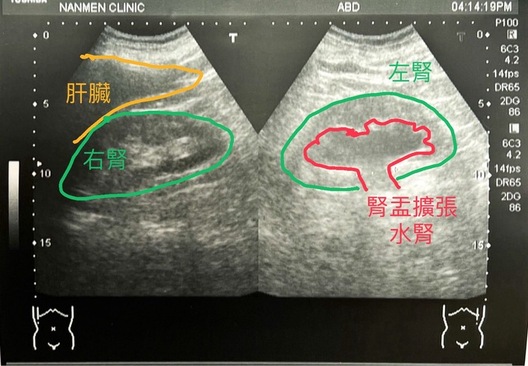

一個約50幾歲男性左側腰痛進診診間,於是安排了超音波檢查。

於超音波檢查後發現左側腎臟水腫,故進一步轉診醫院治療。

腎臟水腫(Hydronephrosis)也稱為水腎或腎積水,從字面上來看,像是腎臟淹水,但其症狀是腎盂擴大,導致尿液都積在腎盂中。

1.超音波檢查:最常用的檢查方法之一,它可以快速、無痛地觀察腎臟結構,檢測是否有腎盂擴張。可以透過超音波可以評估腎臟大小、形狀和尿液滯留情況。